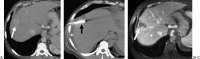

Radiofrequency ablation (RFA) is an alternative therapy for hepatocellular carcinoma and liver metastases when resection cannot be performed or, in the case of hepatocellular carcinoma, when transplant cannot be performed in a timely enough manner to avoid the risk of dropping off the transplant list. RFA has the advantage of being a relatively low-risk minimally invasive procedure used in the treatment of focal liver tumors. This review article discusses the current evidence supporting RFA of liver tumors, as well as the indications, complications, and follow-up algorithms used after RFA.